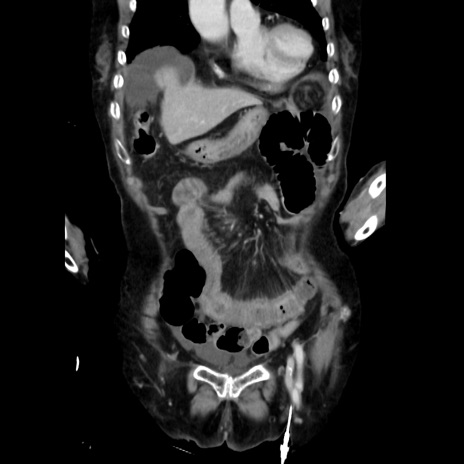

症例40(冠状断像)

【症例】90歳代女性

【主訴】腹痛・嘔吐

【現病歴】 食欲低下、嘔吐があり昨日他院受診。肺炎と診断され入院となる。入院後より腹部全体に圧痛あり。胃管留置され経過みていたが、症状持続するため、

当院転院となる。

【既往歴】胸椎圧迫骨折、胆石症

【身体所見】腹部:中央に激痛あり、圧痛あり、反跳痛不明

【データ】WBC 17100、CRP 18.82

冠状断像